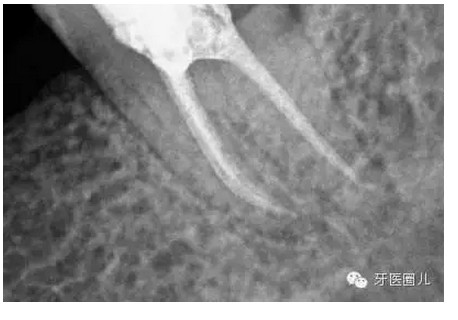

這三個(gè)病例采用protaper器械,最后一個(gè)病例有不足,遠(yuǎn)中舌根根尖2mm有一個(gè)嚴(yán)重的向上彎曲,預(yù)備和充填時(shí)沒有到達(dá),術(shù)前評(píng)估和術(shù)中評(píng)估時(shí)覺得這個(gè)病例難度超過了我的操作范圍,但是患者沒有精力選擇更好的醫(yī)院,我于是和他講明狀況盡量做到我能做的了